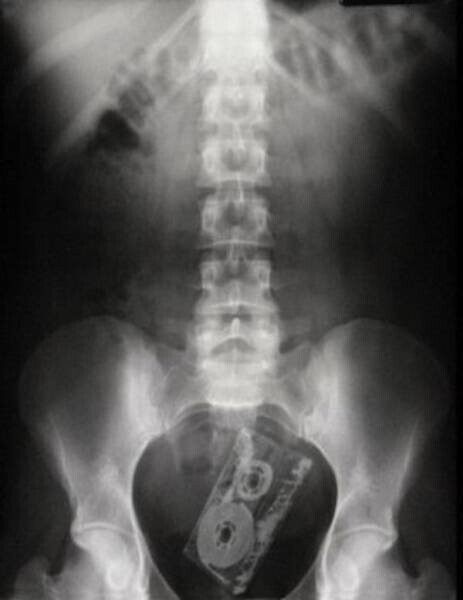

13. Що це таке і як воно туди потрапило?